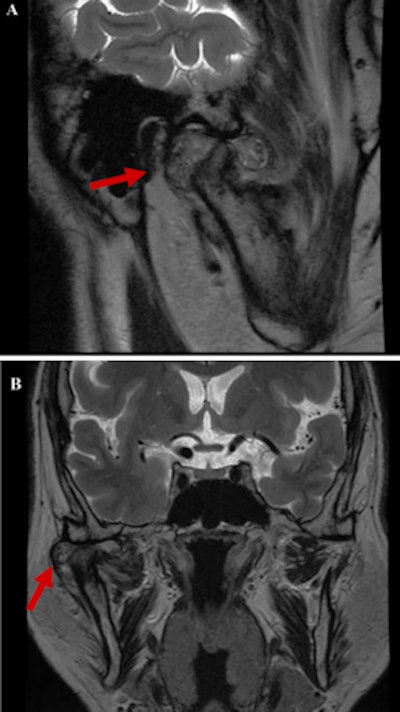

Dental x-rays showed horizontal bone resorption in the upper and lower jaws and extensive calcificationlike opacities in the right TMJ while magnetic resonance imaging (MRI) showed the dilation of the upper and lower joint spaces with differing levels of hypointensity. However, there was no observable disc dislocation in the joint on the right side, and the left side showed nothing abnormal, they wrote.

The man underwent a computed tomography scan that revealed an area of hard tissue that measured 38 mm, multiple rice-grain opacities around the right mandibular condyle, and osteosclerosis of the right articular head with no observable bone resorption, the authors wrote.

Based on the imaging and clinical features, the differential diagnosis was a tumor or a tumorlike disease. To get a definitive diagnosis, a biopsy was done. Upon opening the superior articular space, a mass covered with a fibrous capsule was seen. The mass, which was surrounding the mandibular condyle and had numerous white, cartilagelike hard tissues and chalklike soft tissues of mixed sizes, was removed and sent to the lab for analysis. Results showed that the mass was formed by aggregates of basophilic crystal deposits surrounded by a giant cell reaction, the report's authors wrote.

Since the patient had no history of trauma and imaging revealed joint effusion with multiple calcified loose bodies in a tumorlike lesion with a well-defined border surrounding the lower jaw condyle of the right TMJ and the loose bodies were confirmed by histopathology, the patient was diagnosed with calcium pyrophosphate crystal deposition and synovial chondromatosis, according to the case report.